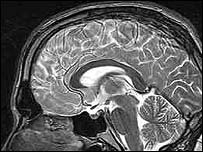

Imagem de ressonância magnética

Supercondutores são utilizados em exames de ressonância magnética

Materiais supercondutores são utilizados, por exemplo, na medicina – em exames de ressonância magnética – e na física – em partículas aceleradoras.

O prêmio de física foi anunciado um dia depois da premiação de Peter Mansfield e Paul Lauterbur, vencedores do Nobel de Medicina por seu trabalho no desenvolvimento da ressonância magnética.

"Certamente, a câmera de ressonância magnética é uma importante aplicação disso (da supercondutividade), e acho que é uma interessante coincidência que o prêmio de medicina tenha ido para uma aplicação enquanto nosso prêmio vai para as descobertas que fizeram o desenvolvimento dessa aplicação possível", disse Oequist à agência de notícias Associated Press.